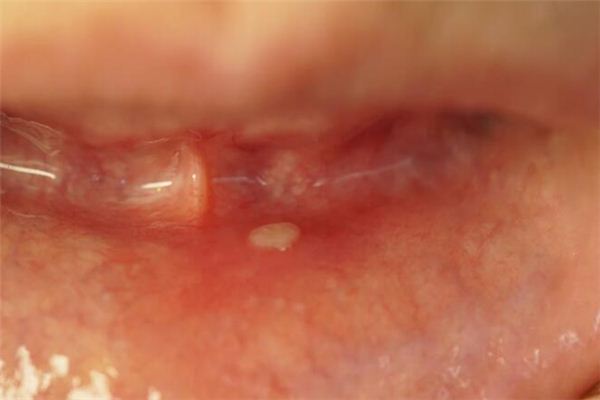

梦见溃烂是什么意思?做梦梦见溃烂好不好?梦见溃烂有现实的影响和反应,也有梦者的主观想象,请看下面由周公解梦官网整理的梦见溃烂的详细解说吧。

梦见任何物体上的溃烂,都是邪恶之梦。